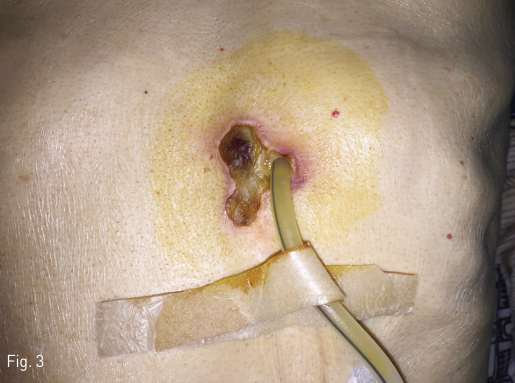

Fig 3

The patient revisited the clinic complaining unhealing wound around the gastrostomy site. About 3 x 2.5-cm sized skin necrosis was noted at the medial aspect of the gastrostomy tube.